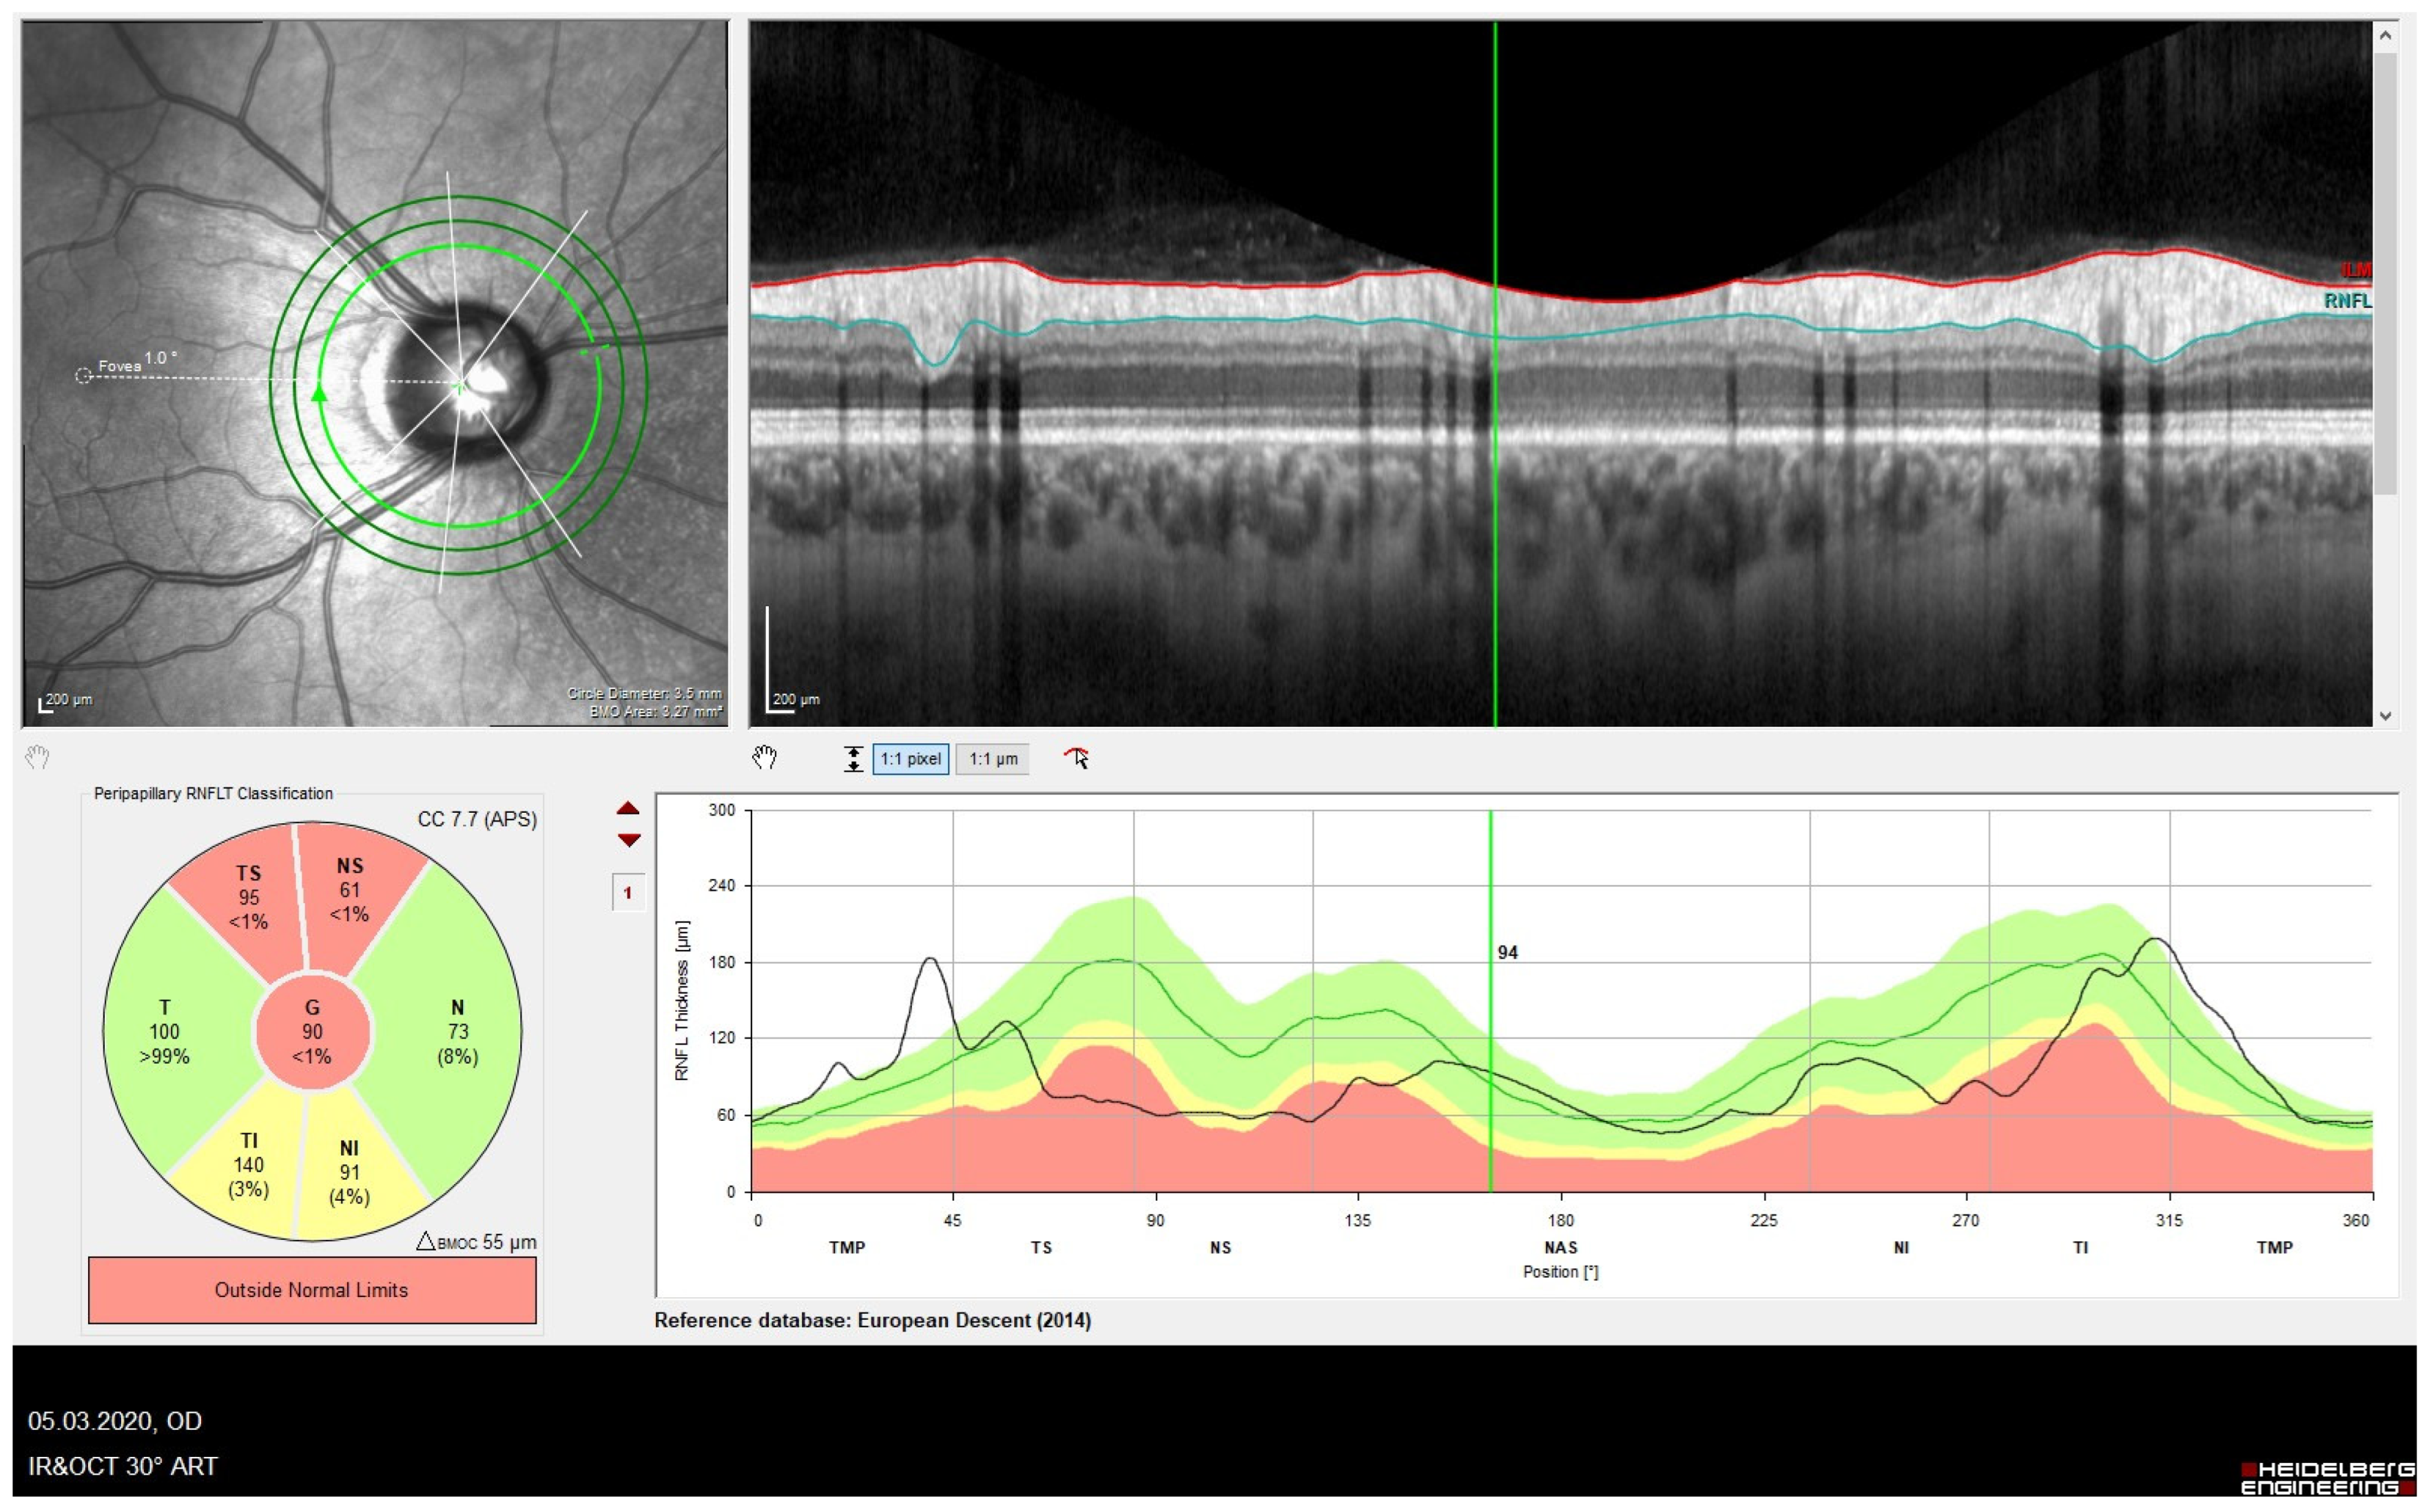

The Retinal Nerve Fiber Layer (RNFL)

- Influence of refraction on the RNFL:

- Influence of ethnicity: